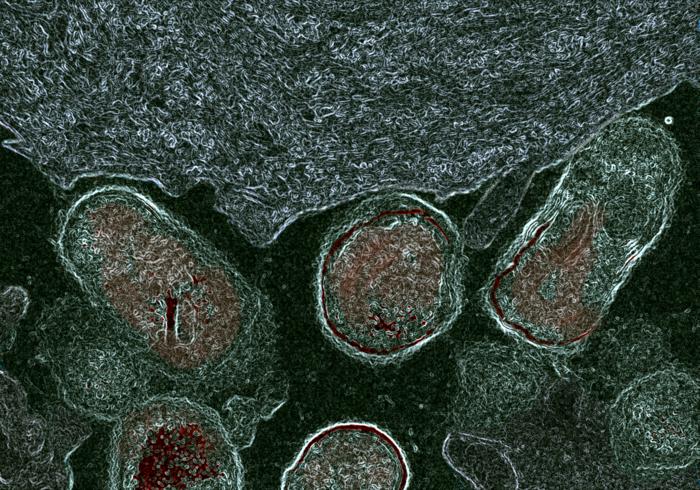

The researchers obtained epithelial cells derived from human vaginal specimens and used them to explore glycan dynamics. With a combination of biochemistry and microscopy techniques, they discovered that in bacterial vaginosis, bacteria release enzymes called sialidases that partially dismantle protective glycan molecules on the surface of epithelial cells. The researchers were also able to induce a bacterial-vaginosis-like state in ‘normal’ epithelial cells by treating them directly with sialidase enzymes produced in the laboratory.

To understand how these bacteria impact vaginal health, the researchers studied the epithelial cells that line the vagina. Because the surface of epithelial cells comes into contact with bacteria and other microbes, it is densely coated with sugar chains, called glycans. Glycans play key roles in cell biology and disease, such as protecting against microbial invasion and helping cells adhere to each other. However, glycans can also be a food source for bacteria.

“We knew that bacterial species implicated in bacterial vaginosis can feed on glycans in secreted mucus. The current study allowed us to look directly at what those bacteria are then doing to the vaginal epithelial surface landscape on a biochemical and microscopic level,” said co-corresponding author Amanda Lewis, PhD, professor in the Department of Obstetrics, Gynecology & Reproductive Sciences at UC San Diego School of Medicine.